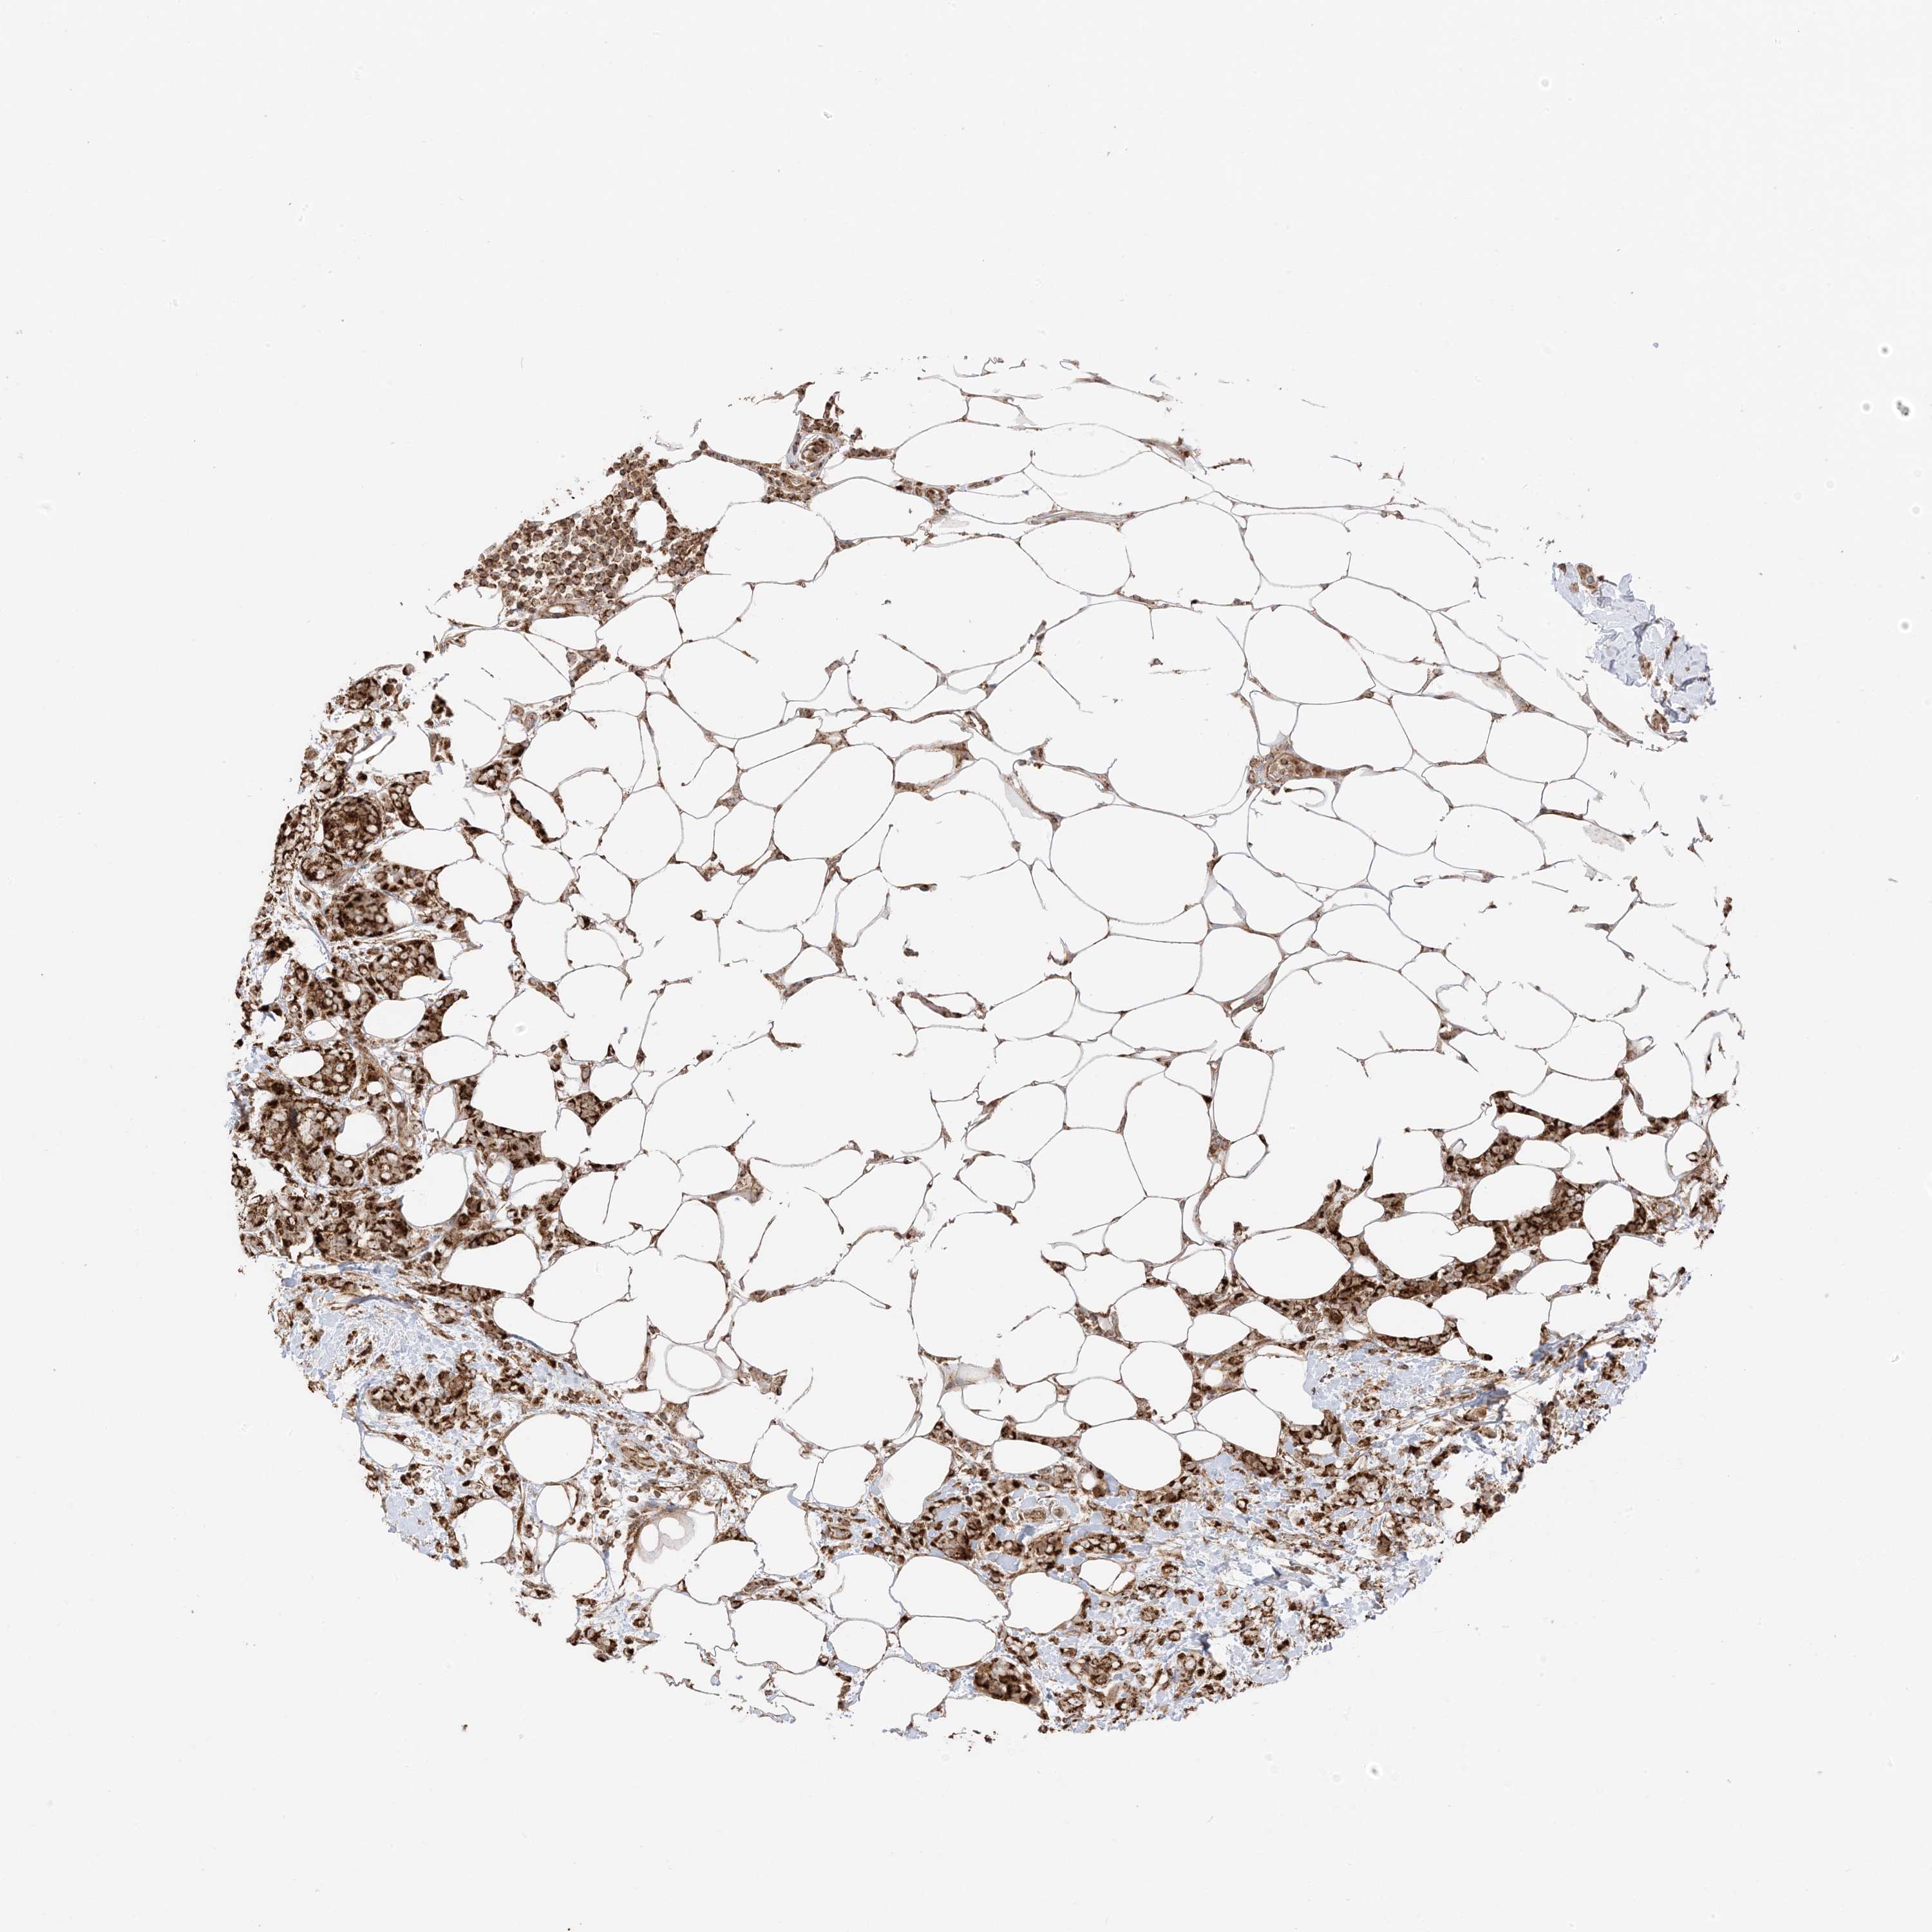

CANCER BREAST CANCER Show tissue menu

BRCA TCGA BRCA VALIDATION PROTEIN EXPRESSION